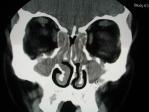

副鼻窦CT扫描 CT检查已经成为诊断鼻窦炎的重要手段,也是鼻窦炎手术前必须做的系列检查之一,CT扫描分为冠状扫描和水平位扫描。鼻窦炎经常和鼻息肉并存,CT可以显示鼻息肉鼻窦炎的范围,清晰显示各鼻窦及其比邻区域的细微结构,为医生诊断和治疗鼻窦炎提供了重要的依据.通过CT,还有助于鼻窦炎与其它疾病如鼻窦癌等进行区别。